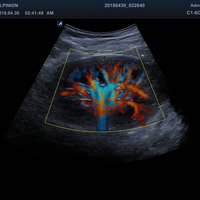

• Farbdoppler: farbige Darstellung der Richtung des Blutflusses

• Powerdoppler: sensitive, farbige Darstellung des Blutflusses unabhängig von Geschwindigkeit und Richtung

• DPDI: Technologie, die Sensitivität des Powerdopplers mit der Flussrichtungsinformation des konventionellen Farbdopplers kombiniert